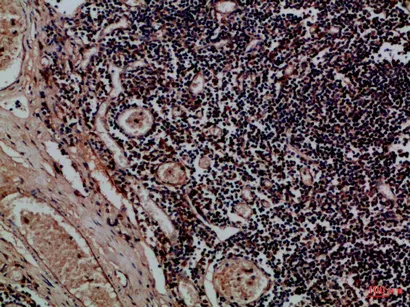

CD24 Rabbit Polyclonal Antibody($99/20μL)

Cat: APRab08302

Application:IHC-P,IF-P,IF-F,ICC/IF,ELISA

Reactivity:Human,Rat,Mouse

Gene Name:CD24 CD24A